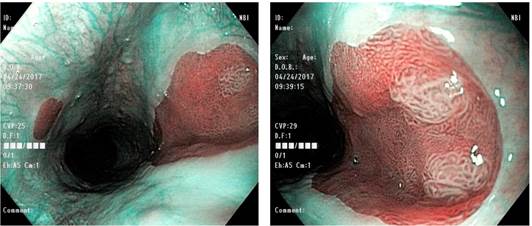

Se trata de un paciente masculino de 41 años con antecedentes familiares de cáncer gástrico materno y antecedentes personales de hemorroidectomía y gastritis crónica. 2 años antes de la consulta recibió tratamiento para Helicobacter pylori. El paciente consultó por un cuadro clínico de 6 meses de evolución, consistente en epigastralgia y pirosis intensa de predominio nocturno. El paciente niega episodios de emesis o sangrado digestivo. Como estudios previos, aportó una gammagrafía de esófago que evidenció al menos 10 episodios de reflujo gastroesofágico, el más significativo fue de 10 segundos, que se extendió hasta el tercio proximal del esófago. Durante la endoscopia de luz blanca, en el esófago cervical e inmediatamente por debajo del esfínter esofágico superior se observaron 2 islas de mucosa similar a la del antro gástrico, de color salmón y con bordes bien definidos; la isla mayor era de unos 18 x 26 mm. En la evaluación con luz de banda estrecha (narrow band imaging [NBI]), estas 2 islas de mucosa columnar se observaron nítidamente y, además, en el extremo superior de la isla mayor se observaron 2 pequeños parches de mucosa blanquecina, ligeramente levantada de aspecto adenomatoso. La cavidad gástrica presentaba una erosión aislada prepilórica y gastropatía crónica con atrofia multifocal (Figura 1).